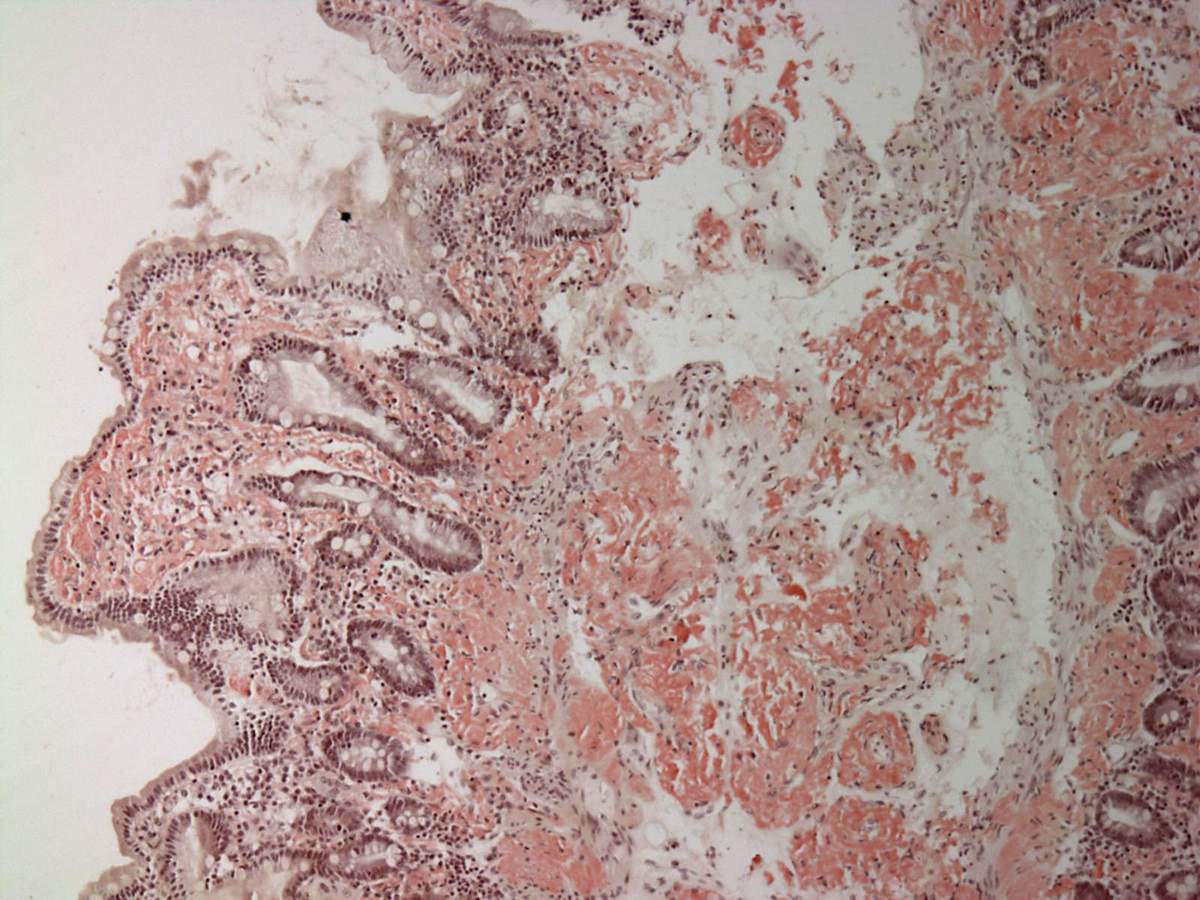

Deposito di amiloide nel duodeno, colorato con il rosso Congo.

Foto di Michael Feldman, MD, PhD University of Pennsylvania School of Medicine.